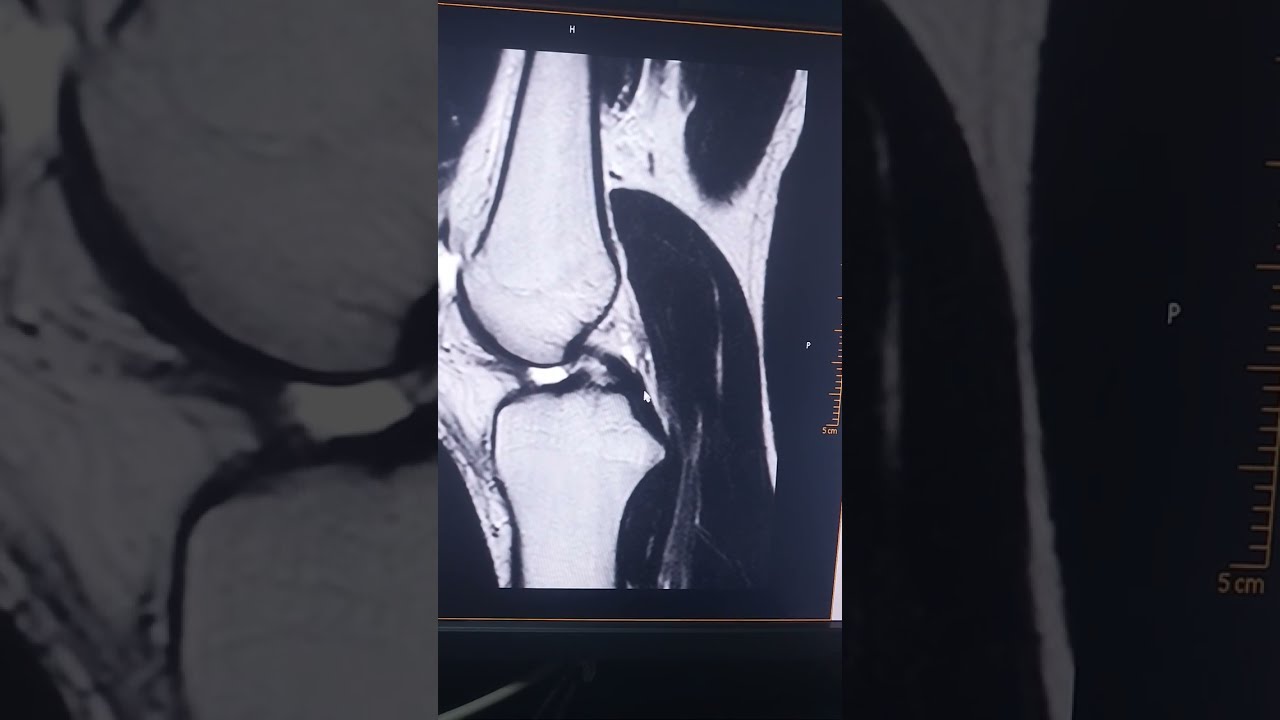

Скачать или смотреть د/ مدحت قاسم ازاي تعرف أن دا قطع في الرباط الصليبي

علامات قطع الرباط الصليبي

• MRI KNEE FOR ACL TEAR                       جزء مهم في فحص الرنين المغناطيسي للركبه

MRI KNEE FOR ACL TEAR جزء مهم في فحص الرنين المغناطيسي للركبه